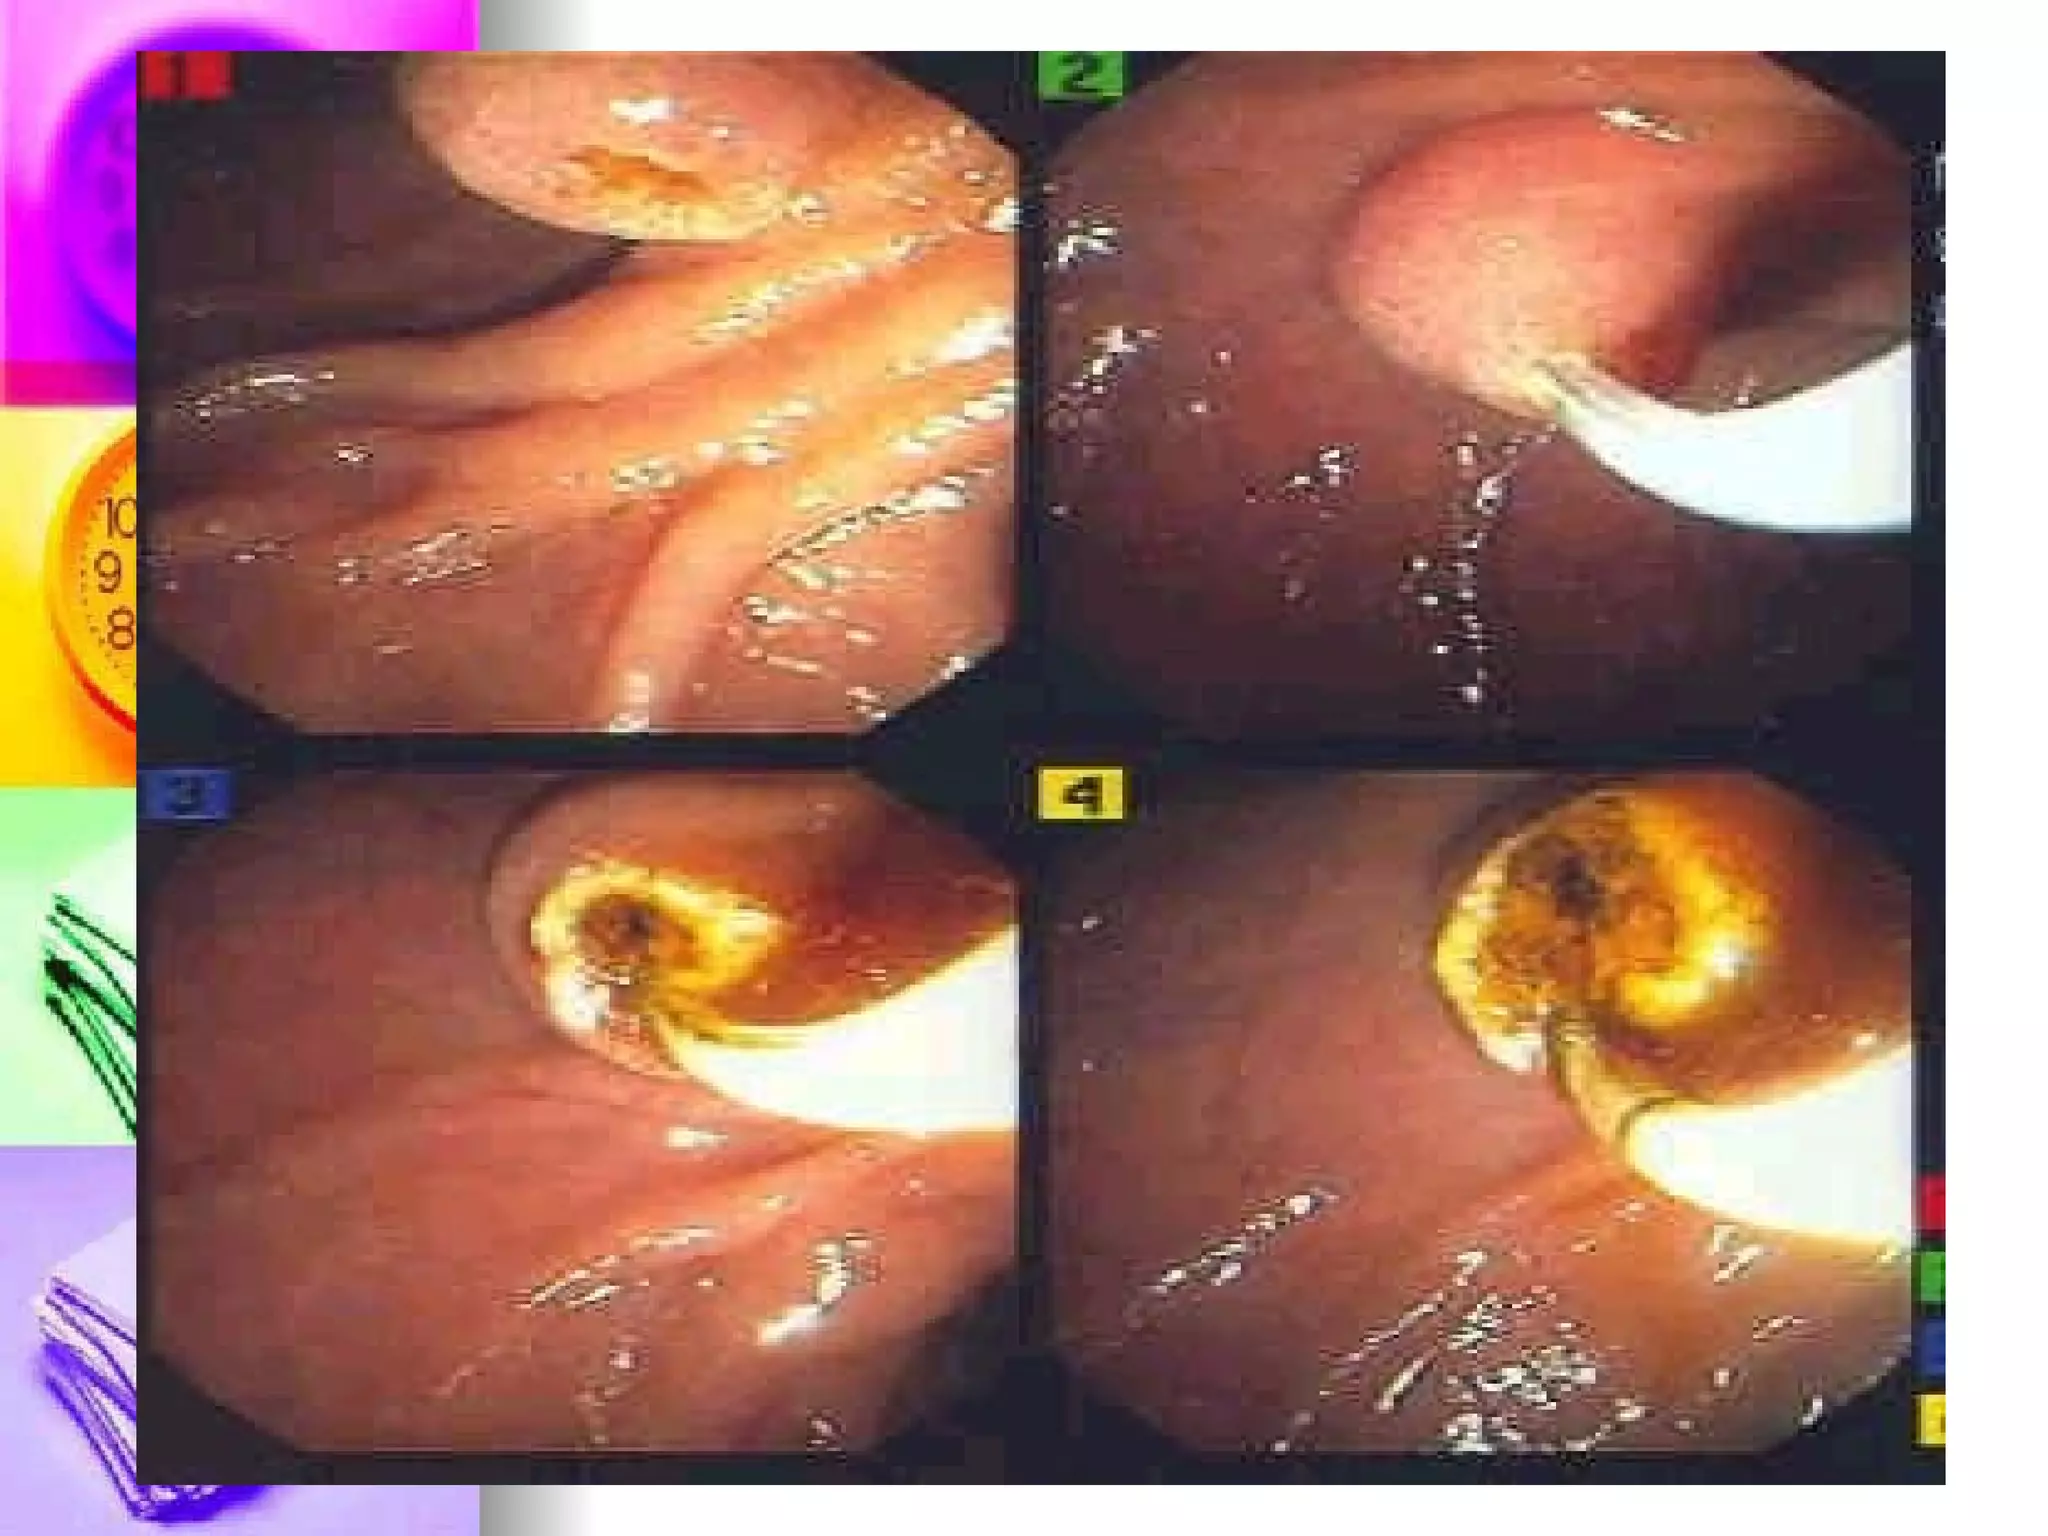

Endoscopic retrograde cholangiopancreatography Examination where a flexible endoscope is inserted into the mouth and via the common bile duct and pancreatic duct to visualize the structures Iodinated dye can also be injected after for the x-ray procedure

Endoscopic retrograde cholangiopancreatography Pre-test: consent, NPO for 12 hours, Allergy to sea-foods, Atropine sulfate Intra-test: Gag reflex is abolished, Position on LEFT side Post-test: NPO until gag reflex returns, Position side lying and monitor for perforation and hemorrhage

Endoscopic retrograde cholangiopancreatographyExamination where a flexible endoscope is inserted into the mouth and via the common bile duct and pancreatic duct to visualize the structures Iodinated dye can also be injected after for the x-ray procedure

Endoscopic retrograde cholangiopancreatographyPre-test: consent, NPO for 12 hours, Allergy to sea-foods, Atropine sulfate Intra-test: Gag reflex is abolished, Position on LEFT side Post-test: NPO until gag reflex returns, Position side lying and monitor for perforation and hemorrhage